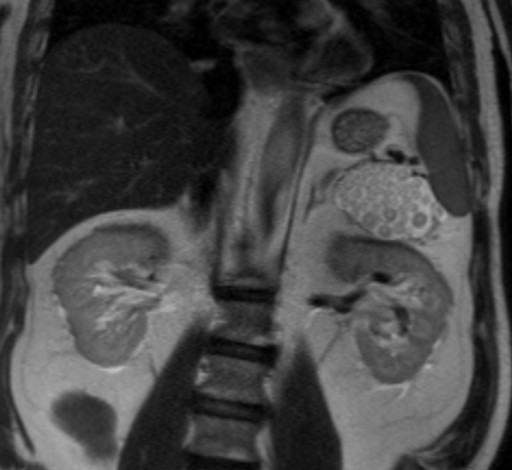

A 63-year-old man with a previous history of colon cancer, resected 3 years earlier, presented for a routine clinical follow-up. Physical examination and past medical history were unremarkable, except for an appendectomy at the age of 15. The patient had had a history of intermittent and mild left upper quadrant abdominal pain not associated with meals before a resection for colonic cancer; CA 19-9, CEA and amylase were unremarkable. There was no body weight loss or fever, and the patient had no previous history of pancreatitis. An abdominal ultrasound was performed which showed a 7 cm non homogeneous anechoic mass at the level of the pancreatic tail. An MR scan was subsequently obtained which confirmed the presence of a 7x4 cm lesion at the level of the pancreatic tail, close to the splenic hylum. This lesion showed a complex structure with multiple sub-centimeter nodules within it. In particular, the lesion was homogeneously hypointense on the pre-contrast T1-weighted MR images (Figure 1), showing a mild rim of enhancement after intravenous contrast administration while maintaining the hypointensity of the central core constant (Figure 2); on T2-weighted MR images, the pancreatic mass had a "cheerios-like" appearance, showing multiple small nodules with a central hypointensity and peripheral hyperintensity; a fluid-level was also present at the bottom of the lesion (Figures 3 and 4), most likely reflecting the inflammatory changes of the lesion. The patient subsequently underwent a distal pancreatectomy and splenectomy (due to the proximity of the lesion to the splenic hylum). Histological examination demonstrated the benign nature of the lesion consisting of a pancreatic lymphoepithelial cyst. The surface of the cyst was smooth, the lesion was filled with keratinous material and the walls were lined with stratified squamous epithelium which was surrounded by a layer of lymphoid tissue composed of small lymphocytes, plasma cells and germinal centers, without signs of atypia (Figure 5). The periphery was composed of normal pancreatic tissue. The postoperative course was uneventful and the patient was discharged from the hospital 10 days after the surgical intervention.

Figure 4. T2-weighted coronal MR image showing a complex mass consisting of multiple sub-centimeter nodules, with a "cheerios-like" appearance, showing a central hypointensity with peripheral hyperintensity. |